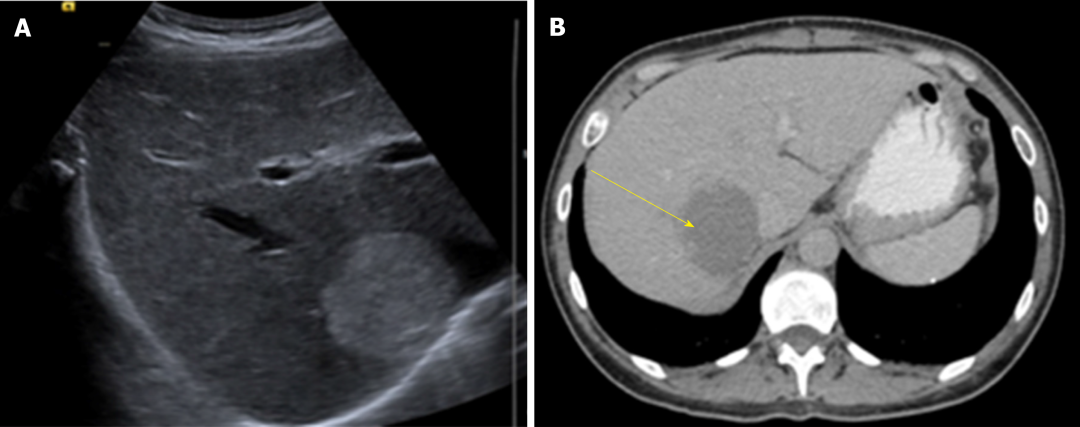

诊断:HH的诊断目前主要依赖于影像学检查,多种检查手段联合应用可提高诊断准确率。常规首选超声检查,再结合CT、MRI以及

图1 肝脏超声(A)和